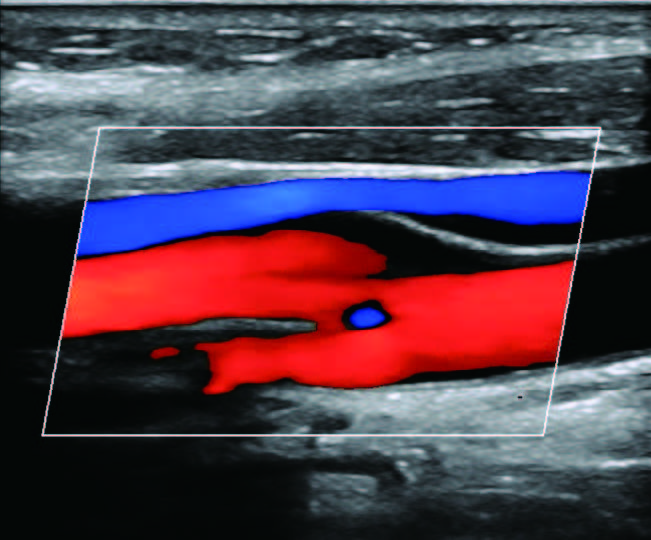

На изображениях, приведенных ниже показаны примеры из клинической практики врачей ультразвуковой диагностики, полученные в процессе апробирования прибора Mindray Resona 7. Приводится наглядные примеры сравнения традиционного режима ЦДК и режима V Flow (Vector Flow).

Изображена яремная вена и бифуркация сонной артерии. CAA, ICA и ECA показаны на одном изображении. В режиме ЦДК отсутствует подробная гемодинамика. В режиме V Flow отображаются данные о скорости и направлении движения частиц крови во всей зоны интереса, включая изменения характеристик кровотока в сонной артерии и яремной вене.